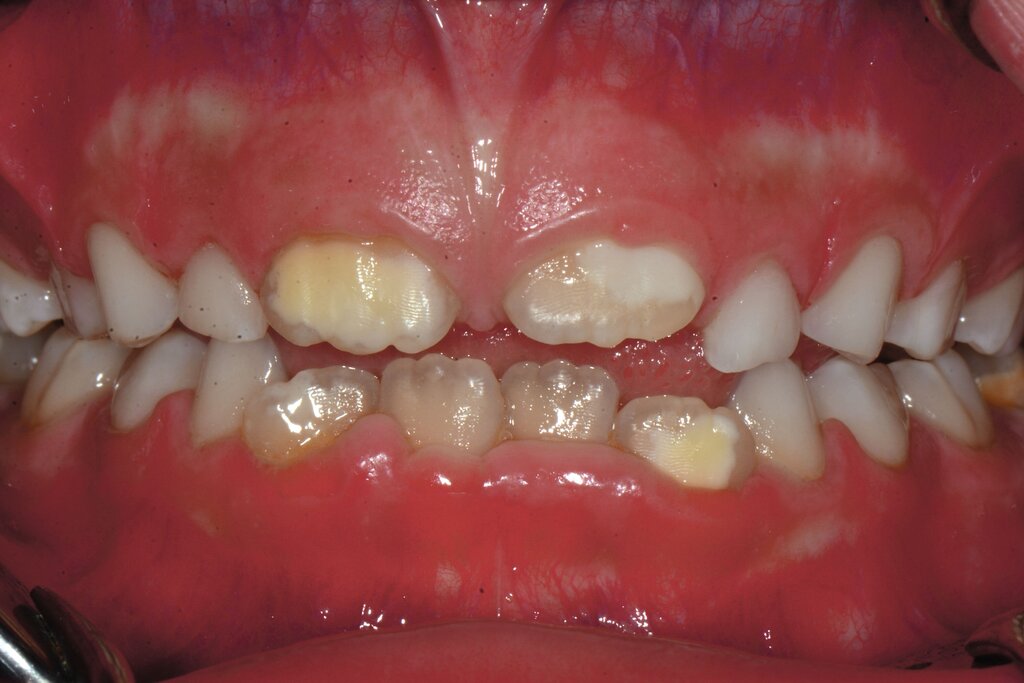

Die MIH (Abbildungen 1 und 2) stellt eine Strukturstörung der Zähne dar, die sich während der Zahnentwicklung manifestiert und daher bereits vor dem Durchbruch des Zahns in die Mundhöhle vorhanden ist. Obwohl der Name suggeriert, dass die ersten bleibenden Molaren und bleibenden Inzisiven die bevorzugten Indexzähne beziehungsweise Zahngruppen in der bleibenden Dentition sind, nutzt die Definition der European Academy of Paediatric Dentistry (EAPD) ausschließlich die ersten bleibenden Molaren zur Diagnosestellung. Entsprechend dieser Vorgabe muss zumindest ein erster bleibender Molar Zeichen einer MIH-bedingten Strukturstörung aufweisen [Lygidakis et al., 2010, 2022], damit die Diagnose einer MIH gestellt werden kann.

Das klinische Erscheinungsbild an bleibenden Zähnen zeigt typischerweise weißlich-gelbe bis gelblich-braune Opazitäten, die zumindest in einigen Bereichen durch eine scharfe Abgrenzung (engl.:„demarcated opacities“) zum gesunden Zahnschmelz charakterisiert sind (Abbildungen 3 und 4). Die abgegrenzten Hypomineralisationen befinden sich mehrheitlich im Bereich der inzisalen Kronenhälfte unabhängig von dem Auftreten an Front- oder Seitenzähnen. Die Ausprägung am Zahn kann dabei auf einzelne Areale oder Höcker begrenzt sein.

Bei einer schwerwiegenderen Ausprägung sind Zahnflächen vollständig betroffen, mitunter alle Zahnflächen an einem Zahn. Die Verteilung in der Dentition beziehungsweise an den Indexzähnen ist gleichermaßen variabel und betrifft nicht nur die Defektgröße, sondern auch die Farbe und Festigkeit. Was die Festigkeit betrifft, gilt als die Faustregel: Je dunkler die Farbe des Schmelzes, umso weicher beziehungsweise poröser und damit minderwertiger wird dessen Qualität sein. Damit reduziert sich seine kaufunktionelle Belastungsfähigkeit, was insbesondere an ersten bleibenden Molaren von klinischer Relevanz ist.

MIH-typische Befunde finden sich aber nicht nur an ersten bleibenden Molaren oder bleibenden Frontzähnen, sondern prinzipiell an allen Zähnen im bleibenden Gebiss als auch in der Milchzahndentition. Da Hypomineralisationen im Milchgebiss vornehmlich an den zweiten Milchmolaren festzustellen sind, werden diese als Milchmolaren-Hypomineralisation (MMH), Decidous-Molar-Hypomineralisation (DMH) oder Second-Primary-Molar-Hypomineralisation (SPMH) bezeichnet. Obwohl die Namenswahl darauf hindeutet, dass es sich um eine eigene Erkrankungsgruppe handelt, ist davon auszugehen, dass diese Krankheitsbilder zum Formenkreis der MIH gehören.